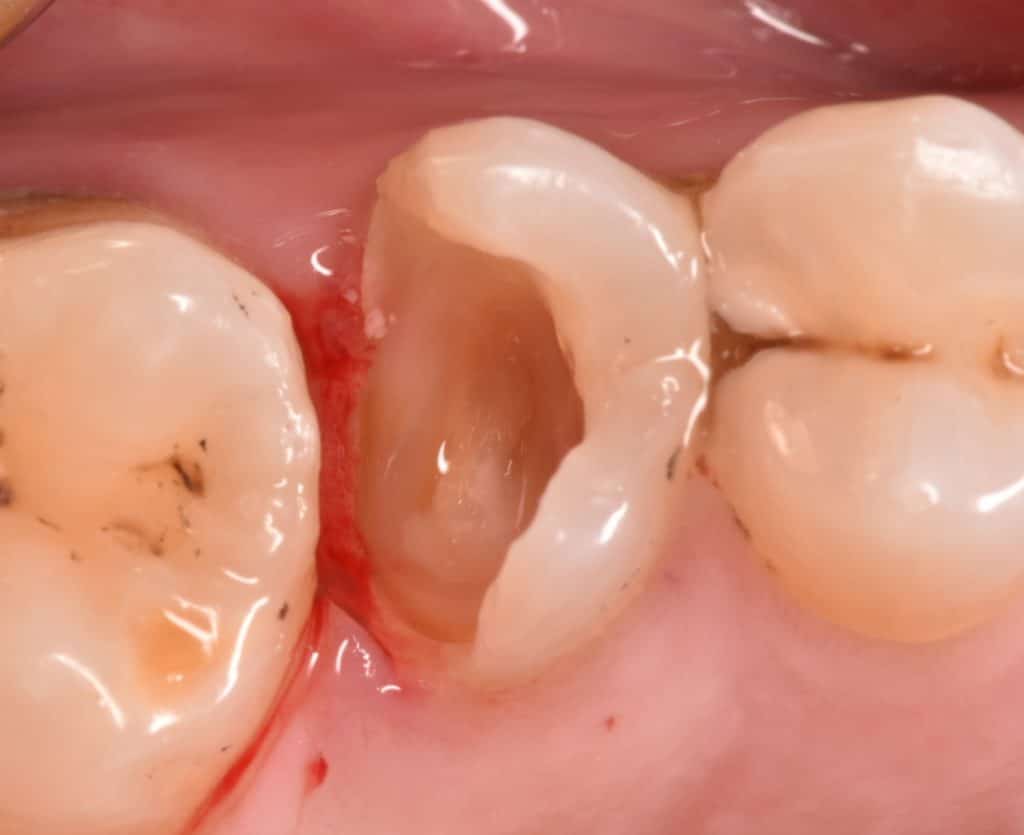

Initial deep marging Cl ll cavity

Saddle metal band for deep margin

Marginal elevation

Band in place , contact point